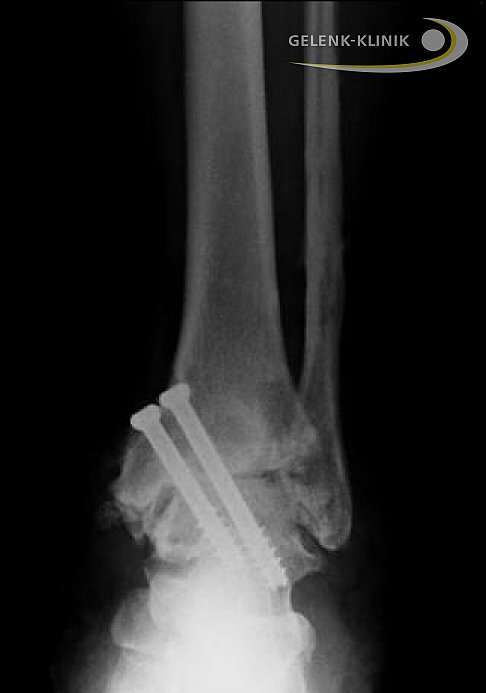

Arthrodese des Sprunggelenks statt Wechsel der Prothese

Versteifung des Sprunggelenks nach Revision einer Sprunggelenksprothese. Bei diesem Patienten erfolgte die Versteifung des oberen Sprunggelenks mit Hilfe einer Plattenosteosynthese. Die Platten werden von außen gegen das zu versteifende Gelenk geschraubt, um die Gelenkpartner in Position zu halten. © Gelenk-Klinik

Auch nach einer Prothesenversorgung kann die Versteifung des oberen Sprunggelenkes als Revisionsoperation eine Rolle spielen. Eine Sprunggelenksprothese kann aus mehreren Gründen versagen: Abnutzung, Fehlpositionierung oder ungenügende Herstellung einer prothesenverträglichen Sprunggelenksachse. Wenn die Sprunggelenksprothese nicht mehr funktioniert, besteht die Therapie der ersten Wahl natürlich Behebung in der der Ursachen für den Prothesenverschleiß und Prothesenwechsel. In manchen Fällen muss nach Ausbau der Prothese das Sprunggelenk versteift werden. Nach dem Versagen einer Sprunggelenkprothese müssen wir immer damit zurecht kommen, dass ein Teil der Knochensubstanz an Talus (Sprungbein), Tibia (Schienbein) und Fibula (Wadenbein) abgetragen wurde, um den erstmaligen Einbau der Prothese zu ermöglichen. Bei einer erneuten Prothesenverankerung steigt also die Wahrscheinlichkeit von Problemen bei der Verankerung. Dazu gehört beispielsweise eine Fraktur der Sprunggelenksgabel aus Mangel an verfügbarer Knochensubstanz. Scheint uns dieses Risiko nach Untersuchung der verfügbaren Knochensubstanz zu hoch, wählen wir eher die Versteifung als sichere Alternative zum Prothesenwechsel.